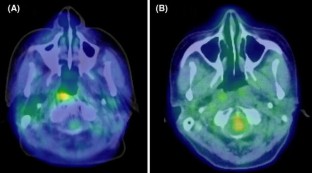

Fig. 1